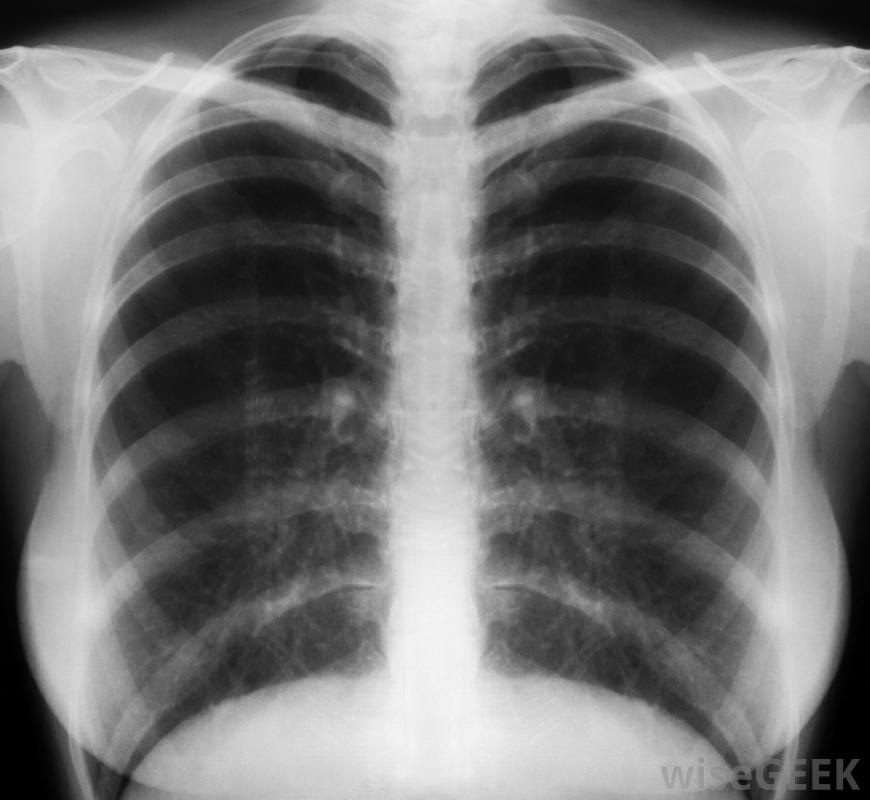

胸部x光片用于确认气胸的诊断当一个肺在没有任何已知原因的情况下塌陷时,它可以被称为自发性气胸。在某些情况下,肺组织内的一个小气囊,称为水泡,可能破裂。从这个破裂的囊中漏出的空气可能会泄漏到肺周围的空腔中。泄漏的空气经过一段时间的积累,可能导致部分或完全的肺塌陷,这取决于压迫它的空气量气胸患者可能会逐渐出现症状。与肺功能衰竭相关的常见症状包括呼吸急促和伴有咳嗽或深呼吸的剧烈胸痛。一些患者可能会在很少用力的情况下容易疲劳或出现心率加快。其他症状可能包括由于氧气不足,血压低,皮肤呈浅蓝色,以及胸闷的感觉。气胸通常可以通过听诊器辨认出来,因为呼吸音可能减弱或不存在。诊断测试可以用来确认气胸已经发生并评估其严重程度。可进行胸部X光检查,以确定受影响肺周围的空洞中是否有空气积聚。在某些情况下,可进行动脉血气分析(ABG)来测量血液中的二氧化碳和氧气水平肺塌陷的治疗取决于肺塌陷的程度和个人的整体健康状况。如果塌陷很小,可对其进行监测,并使其独立愈合。对肺塌陷程度较轻的患者,可给予补充氧气并指导其休息。可使用针头清除积聚在肺周围空间的空气,以减轻任何外部压力那些经历了接近完全性或完全性肺衰竭的患者可能需要放置胸腔导管来排出逸出的空气胸导管位于肺部附近的肋骨之间,可能会在几天内保持原位,需要延长住院时间。在胸腔导管促进受影响肺的重新扩张的同时,可以给予补充氧气。严重的气胸病例可能需要进行肺外科手术以纠正塌陷并防止未来复发。一个人的预后取决于肺衰竭的程度及其原因。那些有气胸病史或吸烟的人将来肺衰竭的风险会增加。与肺有关的并发症塌陷包括反复塌陷和休克。